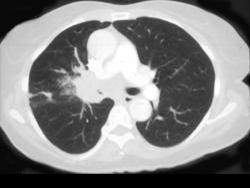

问题 男,56岁,咳嗽,咯血1月余,有吸烟史30余年,结合CT检查选出最可能的诊断 ( )

选项 A、肺错构瘤 B、中央型肺癌 C、肺炎 D、结节病 E、肺结核

答案 B